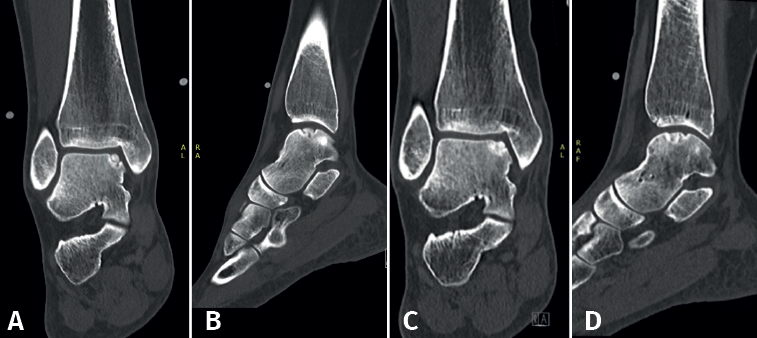

Figura 2. Tipos de morfologías de las lesiones osteocondrales del astrágalo observados en tomografía computarizada en vista coronal y sagital. A: crateriforme; B: quística; C: fragmentaria.

Figura 5. Tomografía computarizada preoperatoria (A y B) y postoperatoria al año (C y D) de un paciente tras la fijación.